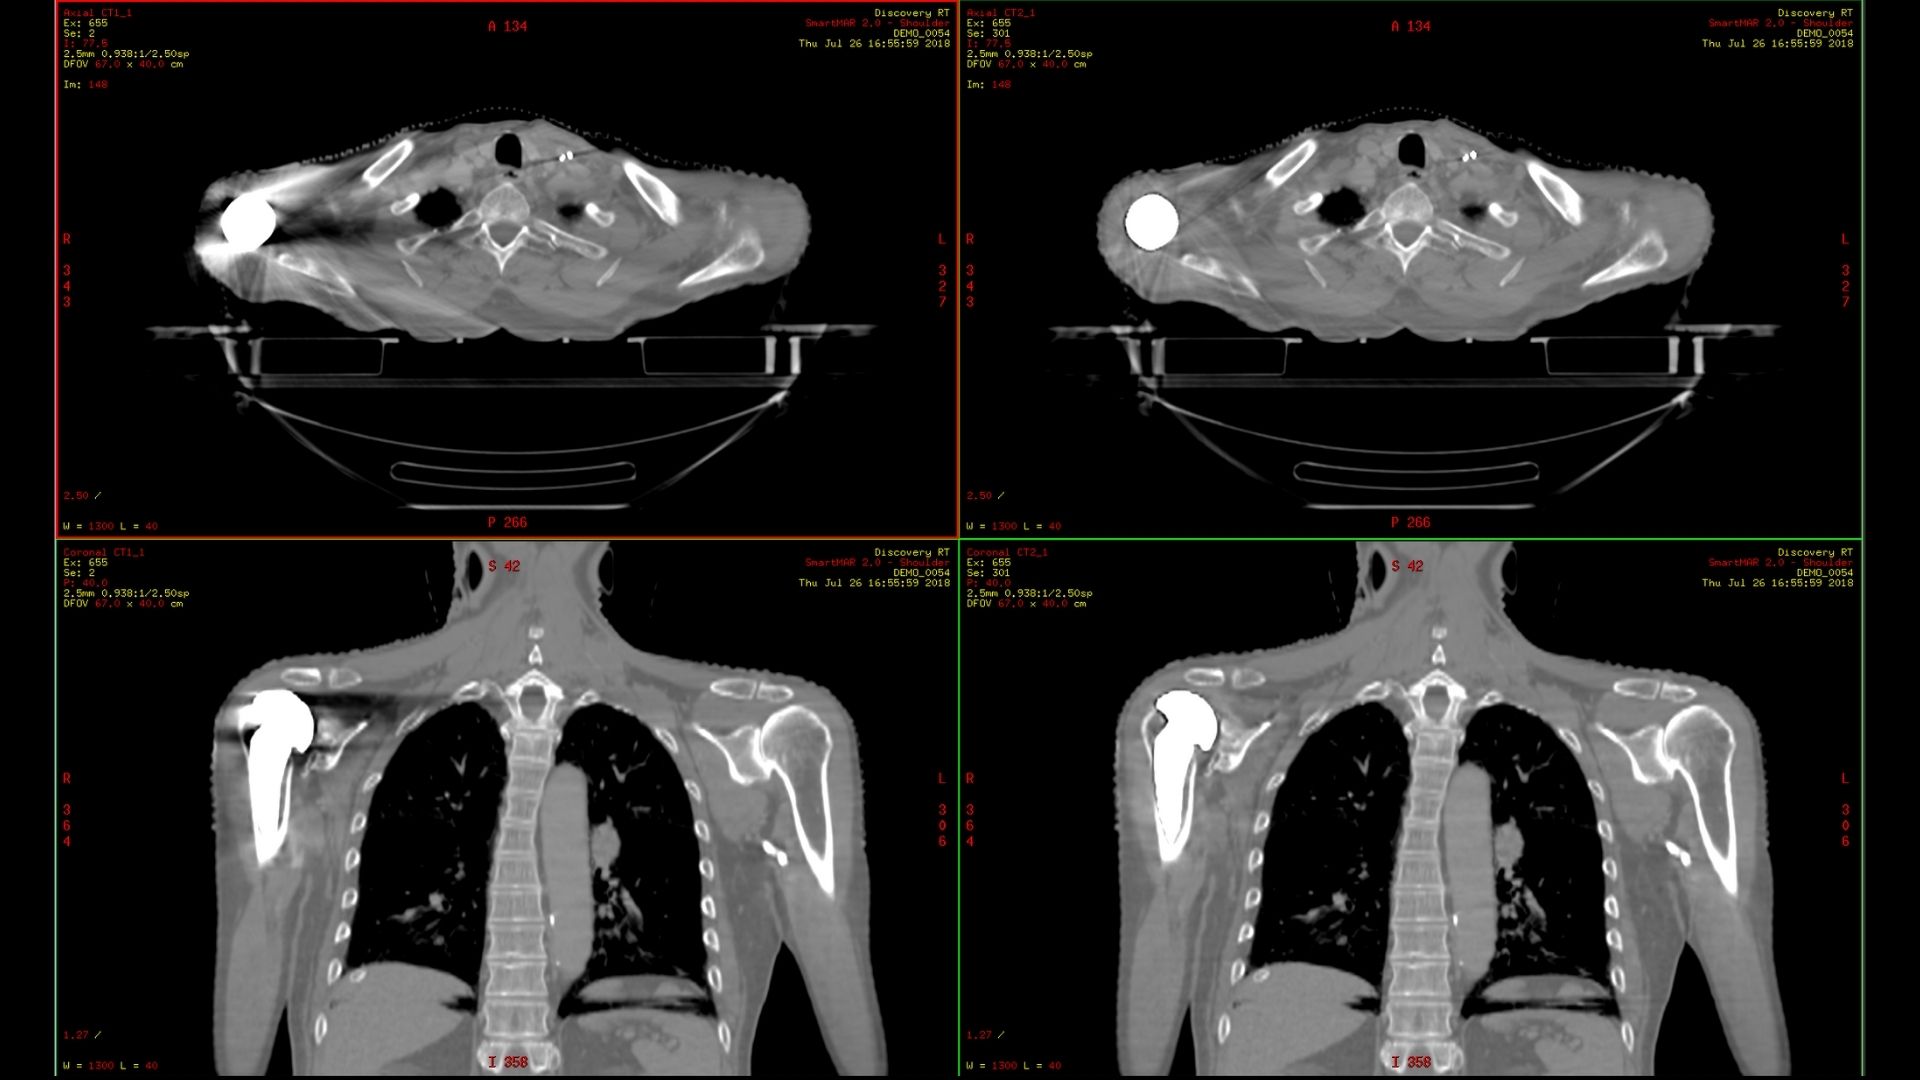

MaxFOV 2

The unique needs of radiation oncology make it important to have image data across the entire bore of the CT simulator. MaxFOV 2 uses GE HealthCare’s proprietary deep learning algorithm to build an extended view up to the edge of the bore. With up to 80 cm extended Display FOV (DFOV), MaxFOV2 allows for less limitations and better image quality that include:

• 2mm skin line accuracy and 40HU CT number accuracy of water from 50cm to 70cm DFOV *

• 3mm skin line accuracy and 60HU CT number accuracy of water from 70cm to 80cm DFOV *

*As demonstrated by phantom testing